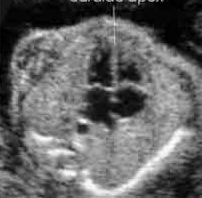

Evaluate fetal situs; what is the presentation of the image?

Cephalic

Breech